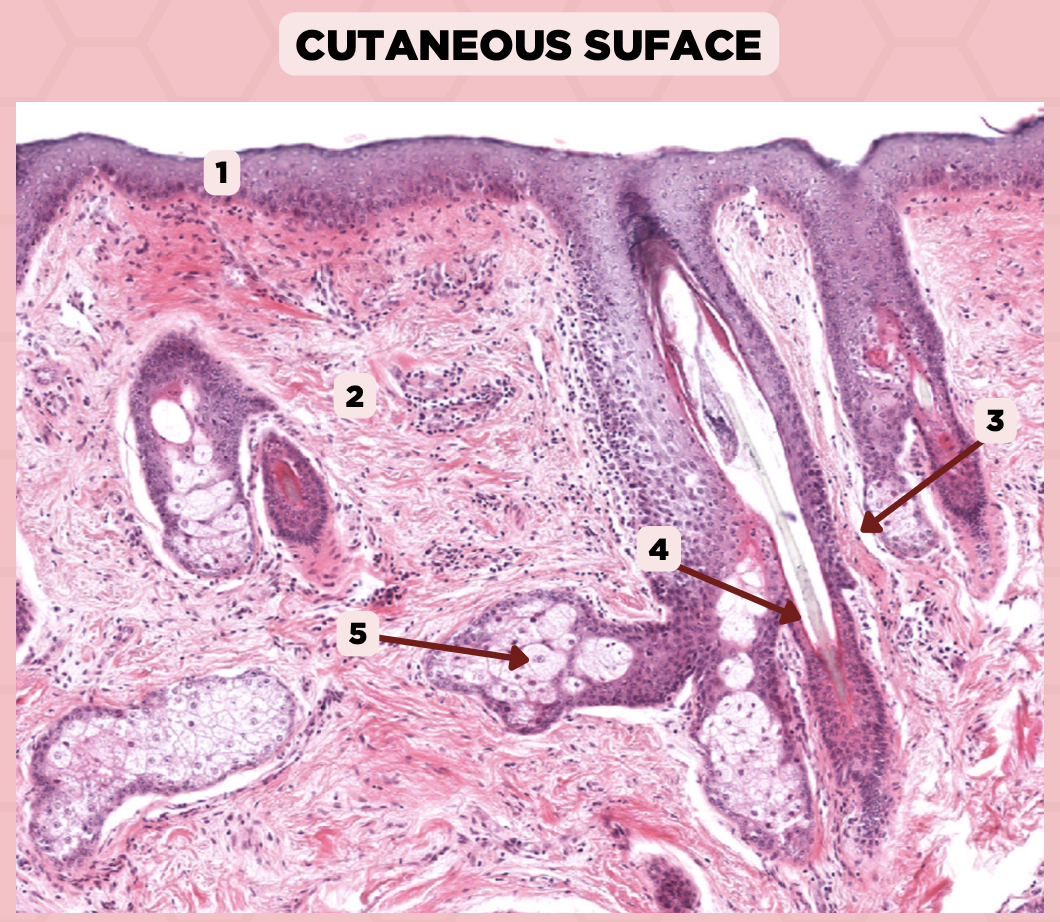

Lip

What is the specimen showed in the picture?

Epidermis

Identify the structure labeled as 1.

Dermis

Identify the structure labeled as 2.

Arrector Pilli Muscle

Identify the structure labeled as 3.

Hair Follicle

Identify the structure labeled as 4.

Sebaceous Glands

Identify the structure labeled as 5.